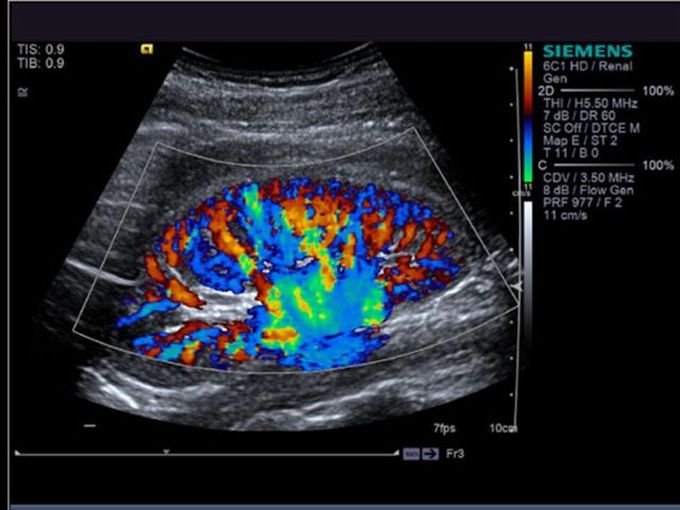

Кроме новой техники, можно заказать восстановленные медицинские системы: ультразвуковые сканеры, томографы, флюороскопы, ангиографы и хирургические установки С-дуга.